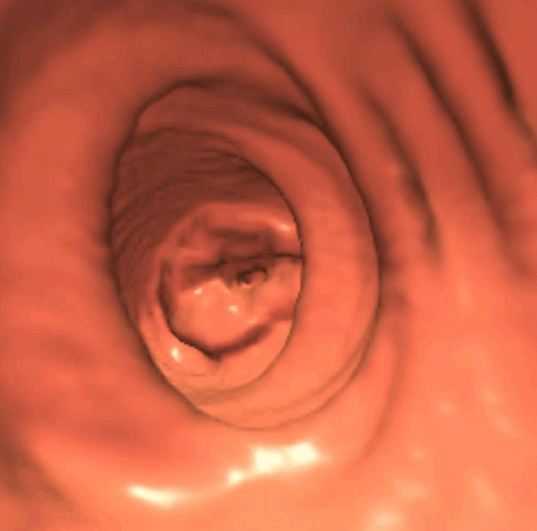

Virtual colonoscopy is a non-invasive, outpatient procedure that takes standard CT images of the abdomen while special software converts those images into a three-dimensional moving picture of the inside of the colon. A specially trained radiologist uses these images to look for polyps or abnormalities.

A cleansing bowel prep is necessary. Any solid material remaining in the colon would make it impossible to identify small polyps. A virtual colonoscopy begins by placing a small flexible rubber tube in the rectum, so that air can be used to expand the colon. While most patients are comfortable during the procedure, some can expect to feel a gas-like fullness. This feeling lasts less than 10 minutes and is gone completely at the end of the exam.

Patients lie comfortably on their back and then turn over onto their stomach while the images are being taken. The procedure takes about 30 minutes from start to finish. Because sedation is not utilized, patients are free to return to home or work immediately without the need for observation or recovery.